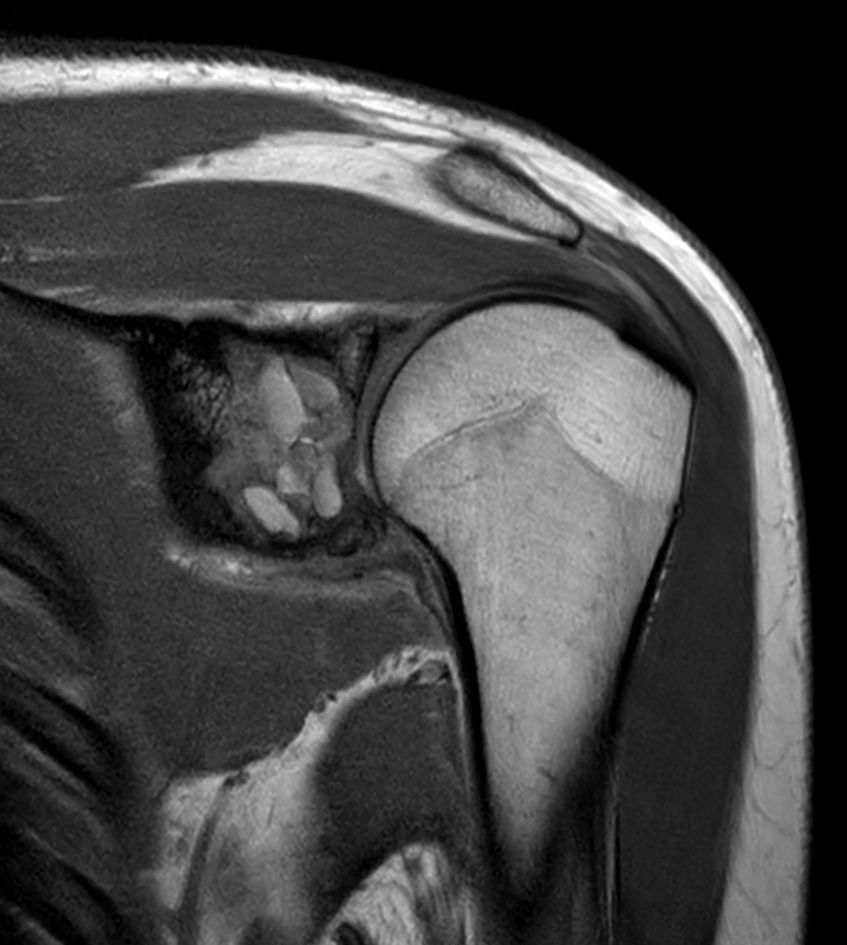

Coronal T1w mDIXON XD TSE - Compressed SENSE (Water only)

Coronal T1w mDIXON XD TSE - Compressed SENSE (In Phase)

Coronal T1w mDIXON XD TSE - Compressed SENSE (Water only) - Post-gado

Coronal T1w mDIXON XD TSE - Compressed SENSE (In Phase) - Post gado